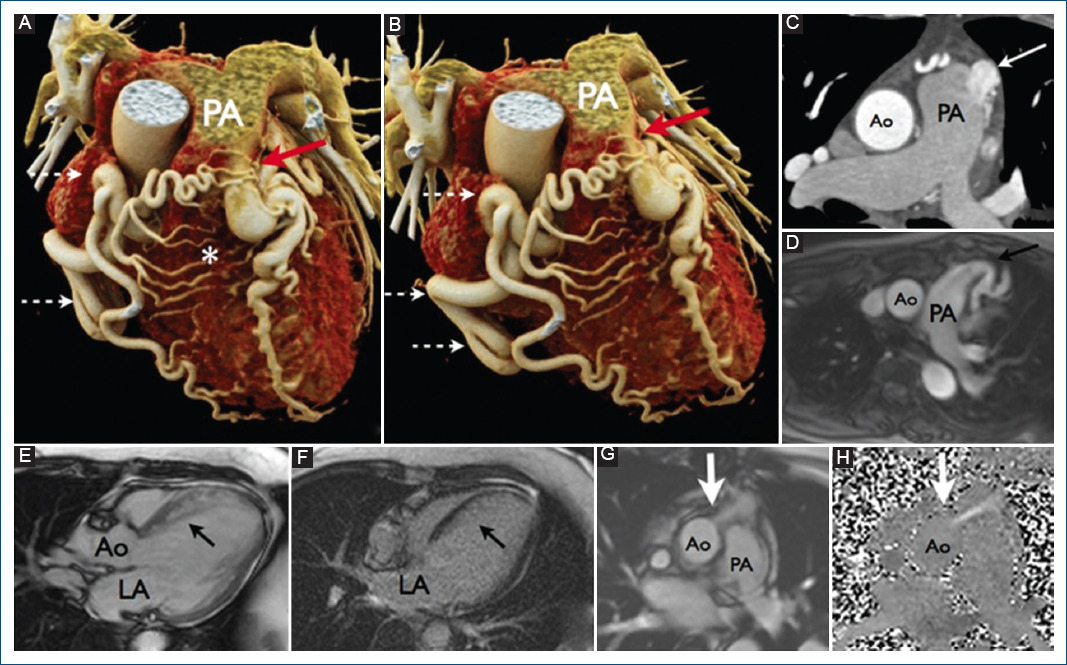

A 53-year-old female presented with Type 2 diabetes, systemic arterial hypertension, and mixed dyslipidemia. She presented at youth intermittent episodes of lipothymia, and for 3 years ago history of angina and v dyspnea on exertion. Her physical examination was unremarkable. ECG showed sinus rhythm, with the left bundle branch block and left ventricular hypertrophy, QS complexes in V1-V2 with poor R-wave progression from V3 to V6. Transthoracic echocardiogram showed left ventricular ejection fraction 50%, dilated left chambers, and eccentric hypertrophy of the left ventricle. Coronary angiotomography showed an anomalous origin of the left coronary artery (LCA) from the pulmonary artery trunk, with diffuse ectasia of the coronary arteries and collaterals formation from the right coronary artery (RCA) to the left anterior descending (LAD) artery and circumflex; without atheroscletic coronary lesions documented and a coronary calcium score of zero (low risk) (Fig. 1). Cardiac magnetic resonance imaging (MRI) confirmed the anomalous origin of LCA from the pulmonary trunk (ALCAPA) or Bland-White-Garland syndrome. MRI was also instrumental in planning the surgical approach1. It allowed for reconstruction of data in any imaging plane, giving complete visualization of complex cardiac anomalies, such as this case. The assessment in this case must involve a variety of imaging modalities that can be used in a complementary way and to increase sensitive, specificity, and predictive values.

In addition, significant angulation of the left main coronary artery and LAD and dilation of the left chambers were noted by the study. Protocol stress-rest with 99mTc-methoxy-isobutyl-isonitrile (99mTc-MIBI) myocardial perfusion SPECT showed anteroseptal and apical non-transmural infarction with mild residual ischemia (Fig. 2). Surgical correction with reimplantation of the LCA to the aorta was performed. The procedure was uneventful, there were no post-operative complications, and the patient fully recovered. The patient has been asymptomatic since the surgical procedure. Cardiac MRI after the procedure showed post-surgical reimplantation of the left main coronary artery to the aorta, no significant changes in the other cardiac structures were noted.

Figure 2 Coronary computed tomography angiography. A, B: volumetric reconstruction the origin of the left coronary trunk from the pulmonary trunk (red arrow), and a significant dilation of the right coronary artery (discontinuous arrows), with multiple collaterals between right and left circulation (*). C: axial section at the level of pulmonary trunk in which the arrow indicates the passage of contrast from the left main coronary artery to the pulmonary artery. D-H: magnetic resonance. D: the left main coronary artery from the pulmonary artery, with posterior angulation of the same (black arrow). E: three-chamber image in diastole where an increase in septum thickness is observed (black arrow). F: with an increased signal intensity in the investment recovery sequence this in relation to collateral circulation. G, H: axial section at the level of the site of reinsertion of the LMCA to the anterior wall of the ascending.